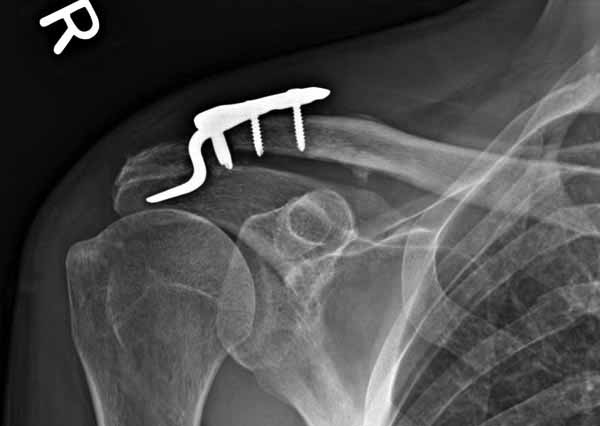

Потом, к сожалению и Юрий, и Вы ошиблись в не существовании такой методики. Открываем AO Principles of Fracture Management\2007\ стр.567-568. Есть еще на сайте АО-травмы Lateral Clavicle≈Dislocations and Fractures≈The LCP Clavicle Hook Plate . Там акцент методики применения ключичной пластинки с крючком именно и при вывихах, и при переломах!!!

Я ставил польскую http://www.chm.pl/pliki/9878cd2387f303265ebad595b2519dce.pdf, но у них еще не опубликована методика

Но это не помешало успешно пациента прооперировать.

Еще раз спасибо Вам и всем форумчанам за внимание к теме и помощь.

1.JPG

60KB (62415 bytes)

Замечание понял, спасибо и нормальные рентгенограммы, молодец!

Вопрос "ключичной пластины с крючком при акромиальных переломах" я буквально понял, что ведется разговор насчет перелома акромиального отростка, т.е. самого акромиона. И поэтому ссылка на Acumed, они делают пластину для акромиона!

Во вторых, это хорошо что нашли длинную пластину, я об этом писал "пластина короткая, не покрывает медиальный диафизарный фрагмент ключицы", и у нас не получилось, пластина не выдержала...